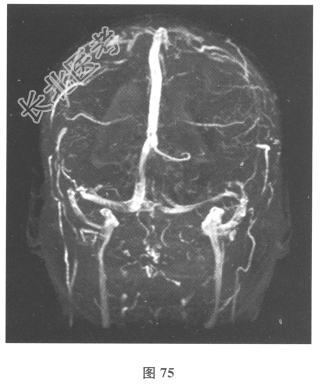

患者入院后复查腰椎穿刺:脑脊液抗酸染色(-),墨汁染色(-),嗜酸性粒细胞比例增高,淋巴细胞体积较大。血及脑脊液弓形虫抗体均(-),血及脑脊液囊虫IgG抗体均(+),莱姆病抗体(-)。追问病史,曾经食用过“米猪肉”。进一步行颅脑MRI检查见图74、图75。)根据上述患者病史和检查结果,对此患者下一步治疗的药物包括